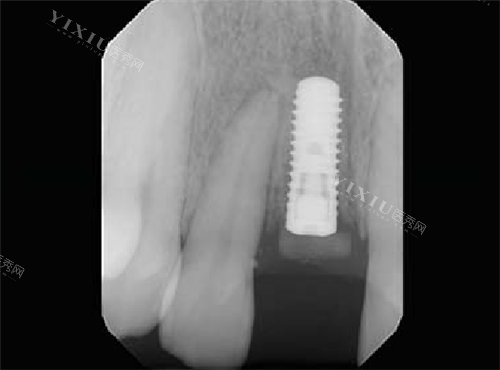

在材料科学方面,BLX采用钛锆合金作为基材,其中锆占比15%、钛占比85%,配合SLActive亲水表面处理技术,在保持较高抗压强度的同时促进骨结合。瑞锆系统则使用钛锆瑞锆合金(Roxolid),通过SLA大颗粒喷砂酸蚀工艺处理表面,其抗折强度达到1000MPa级别,在力学性能上表现出色。